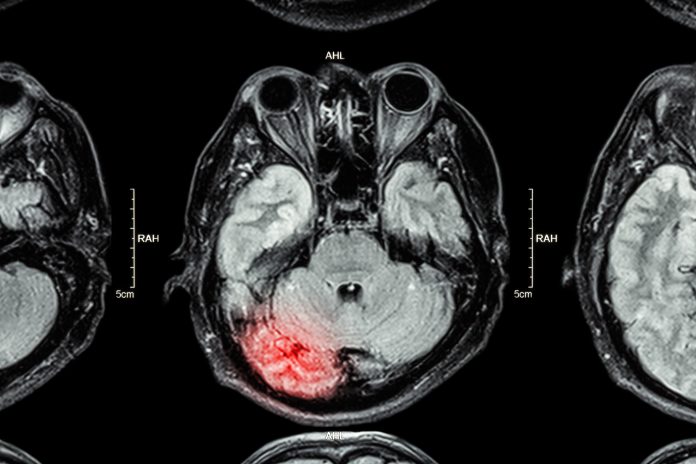

Ruth Smith, COO at Christchurch Group, applauds England’s 27 Major Trauma Centres provision of rehabilitation prescriptions for Acquired Brain Injury care

Hats off to MP Chris Bryant, Chair of the All Party Parliamentary Group on Acquired Brain Injury (ABI) for highlighting and continuing to lobby the Government regarding the poor state of the UK’s neurorehabilitation services since November 2017. Two years on I was delighted to hear that things have at last started to move with the introduction of a new directive to incentivise England’s 27 Major Trauma Centres to complete within 38-72 hours of admission a Rehabilitation Prescription (RP2019) that outlines the needs and care plan for patients when discharged.

It’s definitely a move in the right direction. For ABI patients whose lives have changed forever but are lucky enough to benefit from a neurorehabilitation care pathway it can mean the difference between returning home or a life spent stuck in a care home. But is it enough? What about those ABI patients who are located outside the catchment areas for these Centres – why shouldn’t they benefit from such opportunities, particularly as specialist rehabilitation is one of the most cost-efficient areas of healthcare provision in the NHS?